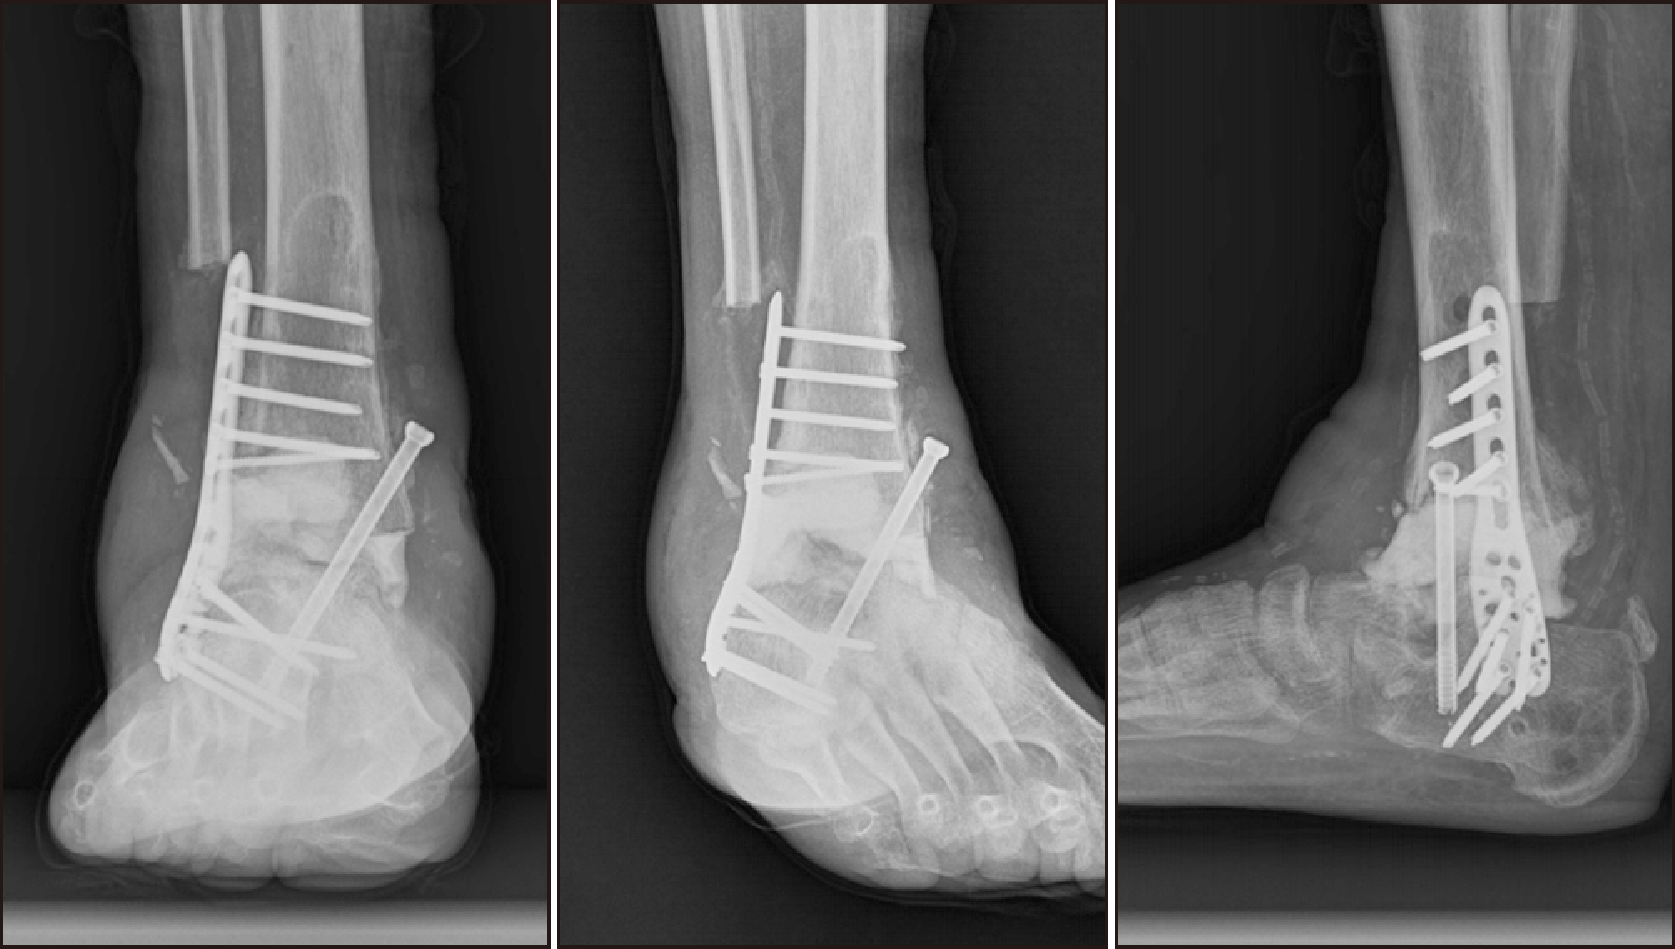

After the stabilization of the acute symptoms, the patient underwent OR/IF. A plate and screws were utilized for the lateral malleolus and K-wires were employed for the medial malleolus. In addition, syndesmotic fixation was performed to stabilize the distal tibiofibular joint (Fig. 3). In this case, K-wire was used for syndesmotic fixation due to the poor soft tissue condition observed around the medial malleolus. While screw fixation or suture anchor may provide stronger stability, the less invasive nature of K-wire was prioritized to minimize additional injury. Additionally, given the risk of poor bone quality we sought to avoid hardware failure or excessive stress. Upon observing a reduction in post-operative swelling, a short leg cast was applied (Fig. 4).

Figure 4

Post-cast radiograph following the application of a short leg cast after the reduction of swelling.